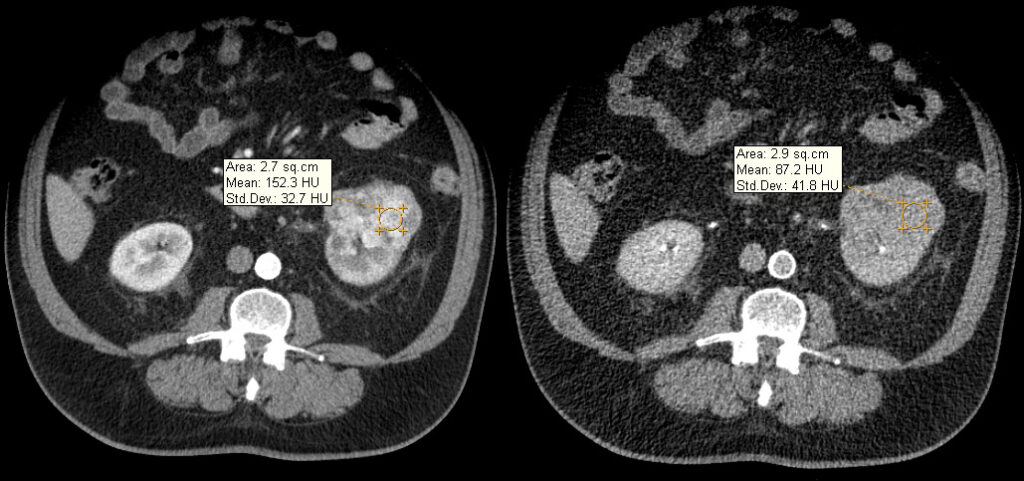

Fase corticomedular y arterial

Esta primera fase ocurre en los primeros 25 a 70 segundos posteriores a la inyección del medio de contraste; la corteza renal, al retener el medio de contraste en este tiempo en los capilares corticales aumenta de una manera intensa diferenciándose de la médula renal, que se encuentra hipodensa.

La fase arterial o corticomedular es esencial para la estadificación, extensión y planificación quirúrgica, si fuese el caso de la neoplasia encontrada, ya que ofrece un mejor detalle vascular (opacificación de los vasos), una mayor definición anatómica y de lesiones vascularizadas en el hígado, el bazo o el páncreas, consideradas dentro del contexto de una metástasis (Fig. 2).

Los errores diagnósticos que pueden presentarse durante esta fase se asocian a lesiones de pequeño tamaño; en el caso de un tumor hipervascularizado pequeño aumentaría su atenuación en la misma medida en que lo haría la corteza. Otro error que puede ocurrir es con los tumores pequeños que se localizan hacia la médula, ya que por su ubicación se mantendrían hipodensos durante esta fase 3-4.

Fase nefrográfica o portal

Se logra a partir de los 80 a 180 segundos posteriores a la inyección del contraste; el medio de contraste se encuentra en los túbulos colectores y asa de Henle durante esta fase y su utilidad se basa en el aumento homogéneo del parénquima renal, lo que permite una mejor delimitación de la masa renal.

Durante esta fase se presenta el mayor realce de los tumores sólidos, por lo que se logra una mejor caracterización de las masas indeterminadas. En un estudio sobre la caracterización de las masas renales menores a 3 cm se concluyó que durante las exploraciones en fase nefrográfica se permitió una mayor detección de lesiones y una mejor caracterización de las masas renales pequeñas que en las exploraciones de fase corticomedular 3-5 (Fig. 3).